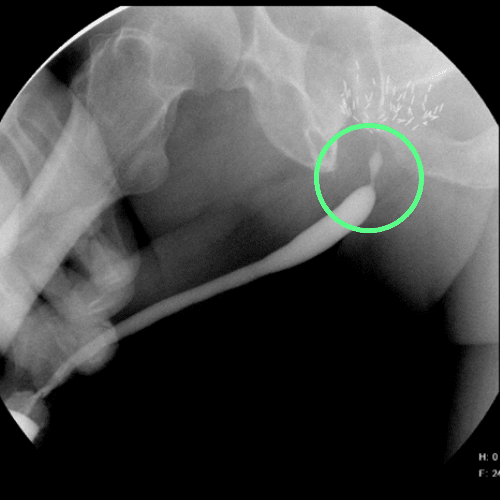

Imagen de cistouretrografía que revela una estenosis de la porción bulbar de la uretra de corta longitud

Cistouretrografía que revela una estenosis uretral en la zona bulbar de corta longitud (marcada con círculo)